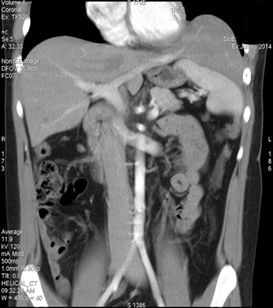

Rysunek 3 21-letni mężczyzna zgłosił się z nawracającymi dolegliwościami brzusznymi, nasilającymi się po spożyciu posiłku. W 4 dobie życia chory operowany z powodu WPP, w wieku 8 lat przeszedł zabieg appendektomii. Kilkukrotnie występowała u chorego niedrożność przewodu pokarmowego, poddająca się leczeniu zachowawczemu. USG jamy brzusznej wykazało strukturę o echogeniczności wątroby zlokalizowaną atypowo – nad śledzioną, bez cech hepatomegalii. Następnie, tomografia komputerowa (TK) jamy brzusznej z kontrastem dożylnym wykazała przemieszczenie lewego płata oraz segmentu IV wątroby do klatki piersiowej nad lewą kopułą przepony.

A 21-year-old man reported for recurrent abdominal pain, impairing after eating a meal. The patient was operated due to CDH on the 4th day of life and at the age of eight he underwent appendectomy. Several times the patient had a gastrointestinal obstruction, undergoing conservative treatment. The abdominal ultrasound showed a structure with liver echogenicity localized atypically – above the spleen, with no sign of hepatomegaly. Subsequently, Computer Tomography (CT) of the abdominal cavity with intravenous contrast showed the presence of the left lobe and segment IV of the liver in the chest above the left dome of the diaphragm.